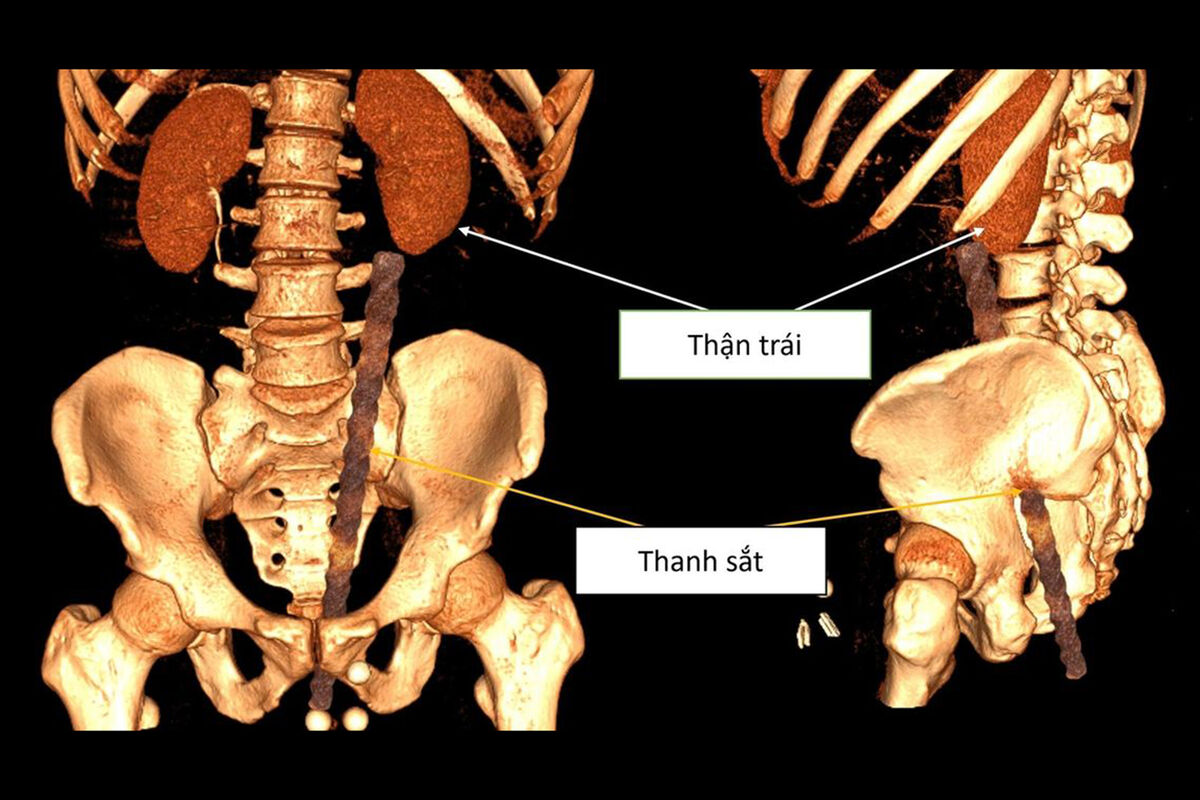

Во вьетнамской провинции Куангнинь 38-летний мужчина был срочно доставлен в больницу после серьезной травмы — металлический строительный прут проник в его тело примерно на 30 сантиметров после неудачного падения, пишет Daily Star.

Обследование показало, что арматура вошла через анальное отверстие мужчины и повредила несколько внутренних органов. По данным врачей, металлический прут вызвал сильное кровотечение в анальном канале, мочевом пузыре и брюшной полости. Также были зафиксированы повреждения органов таза.

Во время операции медики обнаружили, что объект находится опасно близко к поясничной области пациента. У мужчины диагностировали ушиб передней стенки прямой кишки длиной около 3 см, повреждение левого мочеточника, разрыв возле почечной лоханки, а также разрыв стенки левой подвздошной артерии, что привело к сильному внутреннему кровотечению и образованию крупной гематомы.